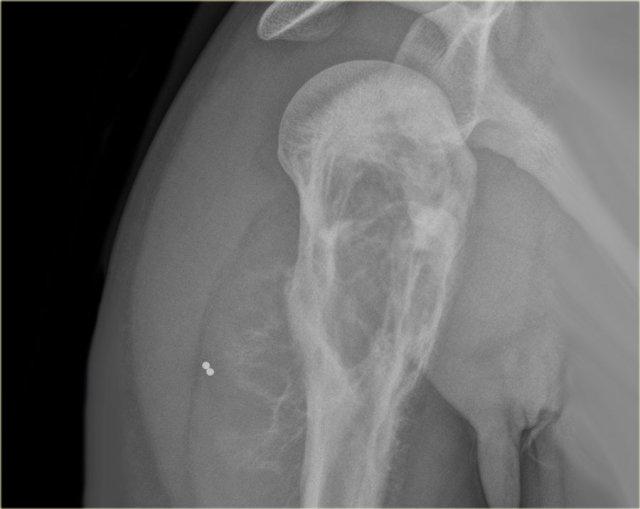

Bên trái là tổn thương hỗn hợp tiêu xương và xơ cứng ở đầu trên xương cánh tay với phá hủy vỏ xương không đều.

Có phản ứng màng xương xâm lấn và khối phần mềm.